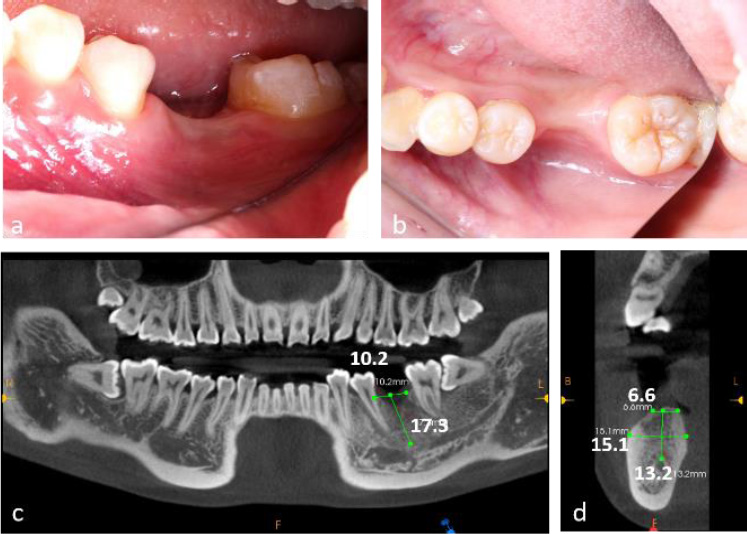

The patient demonstrated good oral hygiene, with a FMPS of 18% and an FMBS of 10%. The edentulous site showed buccal and vertical alveolar bone defects, with no adjacent tooth inclination or opposing tooth elongation (Fig. 1a, 1b).

Cone-Beam Computed Tomography (CBCT) revealed a 4 mm vertical bone defect and an alveolar crest width of 6.6 mm at the edentulous site. The distance from the alveolar crest to the mandibular canal was 13.2 mm (Fig. 1c, 1d). The third molar (tooth 38) was mesioangularly impacted.

Preoperative clinical and radiographic evaluation of a 23-year-old female patient presenting with tooth loss (#36) and concomitant alveolar bone atrophy. (a) Intraoral clinical photograph demonstrating buccal view of the edentulous area, (b) Intraoral clinical photograph showing occlusal view of the defect site, (c) Preoperative cone-beam computed tomography (CBCT) scans, (d) CBCT cross-sectional analysis revealing alveolar crest width of 6.6 mm and basal bone width of 15.1 mm at the edentulous site.